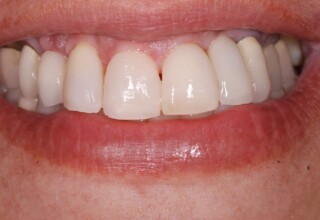

Οι όψεις πορσελάνης είναι ο καλύτερος τρόπος αντιμετώπισης αισθητικών προβλημάτων στην πρόσθια περιοχή του στόματος. Συνδυάζουν συντηρητική αφαίρεση οδοντικής ουσίας και πολύ υψηλή αισθητική απόδοση. Στο παρακάτω εκτεταμένο περιστατικό υπήρχαν: παλαιά σφραγίσματα, δυσχρωμίες, κακό σχήμα και μήκος δοντιών, κακή αναλογία δοντιών-ούλων. Έγινε προσεκτικός εργαστηριακός σχεδιασμός σε εκμαγεία απ’όπου προέκυψαν προσωρινές όψεις που τοποθετήθηκαν στο στόμα για δοκιμή και διορθώσεις. Όταν οριστικοποιήθηκαν οι μετατροπές, οι προσωρινές χρησιμοποιήθηκαν σαν οδηγός για τις μόνιμες. Οι πέντε μόνιμες όψεις πορσελάνης που κατασκευάστηκαν για τα πέντε πρόσθια δόντια της άνω απεκατέστησαν σχεδόν άψογα την αισθητική εμφάνιση της ασθενούς.

Αρχική εμφάνιση

Τελική εμφάνιση